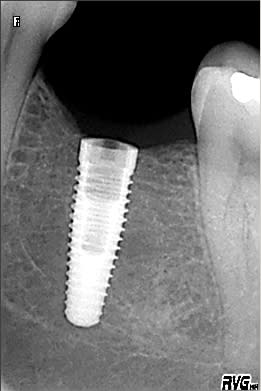

Pour info sur le cas en question, j'ai fini par poser un 4,3 x 13 mm Replace Tapered Groovy (voir radio).

Remarque pour les (plus) novices (que moi) : toujours se méfier du scanner qui n'est vrai que si le patient n'a pas bougé. En effet, sur le scan, j'avais 15 à 16 mm avant le NAI. Après la pose : 1 mm...

Merci pour cette précision Dudulle. Ce qui explique dans ce cas une différence entre l'espace espéré entre l'implant et le NAI (2.5 à 3 mm) et la réalité visible sur la radio jointe plus haut (à peine 1 mm).